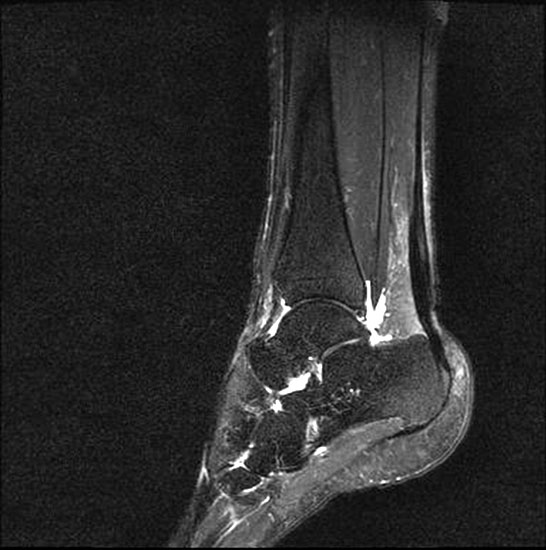

Hier befindet sich ca. 3-5 cm proximal des Tuber calcanei ein als „kritische Zone“ benannter Bezirk, der durch eine ungünstige arterielle Blutzufuhr gekennzeichnet ist (letzte Wiese). Hier finden sich häufig spindelförmige Schwellungen, die bei MRT-Diagnostik nicht selten partielle Nekrosen und Partialrupturen der Achillessehne aufweisen (Abb. 14).

Unabhängig davon können insbesondere chronische Insertionstendinosen der Achillessehne von Partialrupturen (Abb. 15) und erosiven Läsionen des dorsalen Fersenbeines begleitet sein.

Die sonographische Diagnostik eignet sich primär zur Erkennung schmerzhafter Prozesse im Verlauf der Achillessehne und kann bei Bedarf durch Röntgen bzw. MRT ergänzt werden. Besonders bei längeren Verläufen und kräftigen spindelförmigen Schwellungen (>9mm, Normwert <5mm) im Bereich der kritischen Zone sollte ein MRT zum Ausschluss von Nekrosezonen und Partialrupturen vor Therapiebeginn veranlasst werden. Die sonographisch leicht zu erfassende Veränderung der Sehnendicke im mittleren Sehnenanteil ist ein guter Indikator für die Schwere der Erkrankung und die Beurteilung des Behandlungsverlaufes. Die sichtbaren Veränderungen am distalen knöchernen Ansatz der Sehne sind diskreter.

Insbesondere bei größeren Partialrupturen (Abb. 14) sollten operative Verfahren erörtert werden. Kleinere Partialrupturen sind der ESWT gut zugänglich, wie die beiden nachfolgenden Beispiele zeigen: